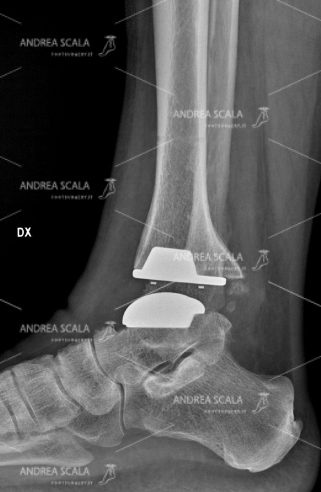

Vediamo, dunque, quali sono i vantaggi di questa operazione e perché è sempre meglio affidarsi al consiglio del dottor Scala e scegliere una protesi una misura. Le ditte che producono le protesi di caviglia hanno tutte messo a punto materiale molto perfezionati dal punto di vista della bio-compatibilità. Alcune protesi sono anallergiche, cioè si possono impiantare nei soggetti con ipersensibilità ad alcuni metalli (nickel). Altre protesi hanno l’inserto mobile, mentre altre hanno l’inserto fisso. Alcune protesi hanno il taglio dell’astragalo piatto , mentre altre hanno il taglio astragalico curvilineo. Il chirurgo deve avere una perfetta conoscenza delle caratteristiche delle protesi e degli strumenti che guidano l’impianto. Il chirurgo deve stabilire la tipologia della protesi che si adatta alle caratteristiche di ogni singolo paziente. Non è possibile mettere un solo determinato tipo di protesi che vada bene per tutti i pazienti.

Il dottor Andrea Scala opera esclusivamente utilizzando delle protesi su misura. Questo perché hanno molti vantaggi che ora vi andiamo a spiegare. In prima battuta occorre ricordare che la protesi di caviglia è composta da diversi materiali come l’acciaio, il titanio e il polietilene. Si tratta di materiali di altissima qualità e affidabilità nel campo medico che, se presi singolarmente, possono arrivare a durare anche oltre cento anni.

Da soli però questi materiali non bastano a determinare la durata della protesi. A indicare il valore concorrono anche – e soprattutto – l’accuratezza del montaggio all’interno dell’organismo che deve essere effettuato con grande cura e precisione.

In particolare, per un corretto montaggio della protesi, occorre rispettare l’anatomia della caviglia, facendo attenzione a conservare le parti anatomiche più delicate, come l’astragalo e i legamenti, nel modo migliore per evitare l’instabilità. In secondo luogo, poi, va rispettata anche la biomeccanica della caviglia, mantenendone l’allineamento. La protesi, infatti, viene stabilizzata ad ogni passo e non subisce carichi asimmetrici.

Una volta scelta la migliore protesi su misura, il dottor Andrea Scala l’applicherà avvalendosi di strumenti di alta precisione, rimuovendo prima l’articolazione malata per poi installare con estrema cura l’impianto selezionato, rispettando la struttura degli arti, l’anatomia e la stabilità.

In questo modo, grazie alla qualità della protesi e alle abilità del chirurgo ortopedico, la protesi durerà diversi decenni. Subito dopo l’operazione al paziente basteranno pochi mesi per riprendere completamente – con una mobilità naturale e senza dolore – tutte le vecchie attività.